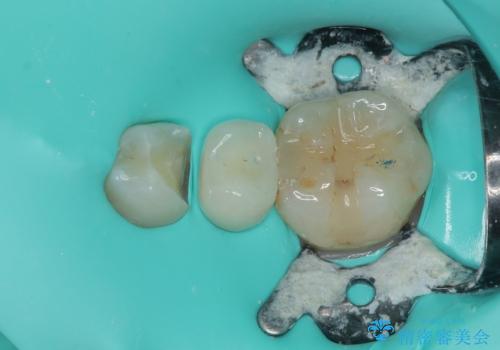

- 左下の被せものが割れたとのことで来院された患者様です。検査の結果、左下の前から4番目の歯はセラミックインレー修復、左下の5番目のところはオールセラミッククラウンによる補綴治療を行っていくことにしました。

拡大鏡視野下で被せもの、虫歯の除去を行い、オールセラミッククラウン、セラミックインレーに適した形に整えました。

セラミックインレーの装着時には、唾液の侵入を防ぐために、ラバーダム防湿を行いました。